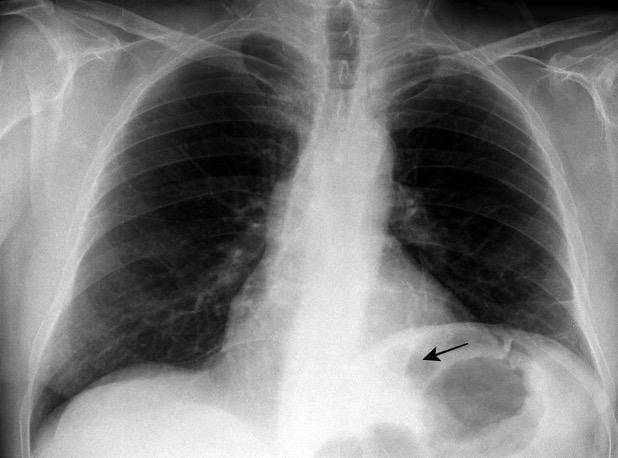

Anillo radiopaco formado por ganglios aumentados. El centro radiotransparente lo constituyen tráquea y bronquios centrales. Más frecuente en Tb y linfoma

Chiarenza et al. Chest imaging using signs, symbols, and naturalistic images: a practical guide for radiologists and non-radiologists. Insights into Imaging. 2019.